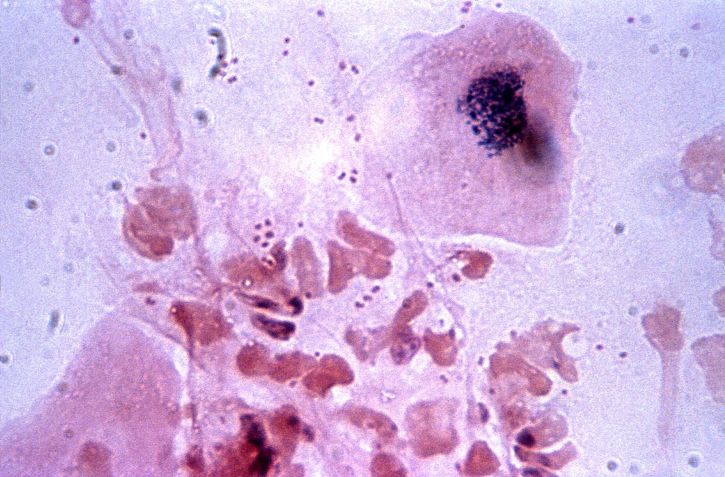

백혈구는 체내의 감염과 싸우는 중요한 세포로, 혈액 1마이크로리터당 4000~10,000개가 정상적으로 존재해야 합니다. 이들 백혈구는 호중구, 호산구, 호염기구 등으로 구성되어 있으며, 그 중 호중구의 비율이 가장 높습니다. 이들은 세균이나 바이러스와 같은 침입자의 공격에 맞서 싸우며 우리 몸을 방어하는 역할을 합니다. 백혈구가 적혈구에 비해 상대적으로 적은 수치에도 불구하고, 그 역할은 매우 중요합니다. 백혈구 수치가 감소하게 되면 체내 감염에 대한 저항력이 떨어지게 되어 다양한 건강 문제가 발생할 수 있습니다.

백혈구는 평소에는 비교적 안정적인 수치를 유지하지만, 여러 외부 요인으로 인해 수치가 떨어질 수 있습니다. 예를 들어, 특정한 약물이나 영양 부족이 백혈구 수치에 영향을 미칠 수 있습니다. 일반적으로 백혈구 수치가 4000개 미만인 경우를 백혈구 감소증이라고 하며, 이때 호중구 수치가 500 이하로 떨어지면 심각한 상태로 여겨집니다. 이러한 상황에서는 즉각적인 대처가 필요합니다.